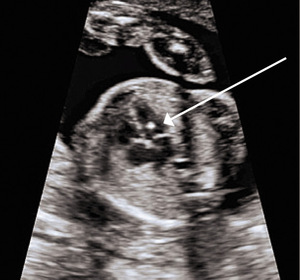

Ognisko hiperechogeniczne w sercu płodu to mały obszar hiperechogeniczny widoczny w komorze serca, którego jasność na obrazie ultrasonograficznym jest równa jasności kości (rycina). Zjawisko to zostało opisane po raz pierwszy w 1987 roku i najczęściej stwierdza się je w lewej komorze, chociaż może również występować w prawej komorze lub obu komorach.1 Uważa się, że EIF odpowiada mikrozwapnieniu mięśnia brodawkowatego. Inne zwierciadlane odbicia w sercu mogą imitować EIF.2 Aby można było uniknąć takiego błędu, ważne jest, aby zobrazować domniemane EIF w wielu płaszczyznach.